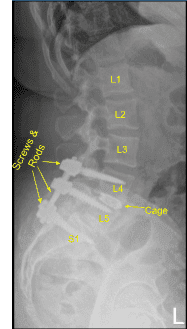

Se colocó un aloinjerto de matriz ósea desmineralizada en el interespacio y luego se colocó un dispositivo intersomal expansible de titanio bajo guía fluoroscópica tras cubrir estérilmente la unidad C-arm. La AP y la imagen lateral mostraron una posición correcta y luego la jaula se amplió hasta el ajuste adecuado, y la radiografía posterior mostró una buena posición tanto en la línea media como en anteroposterior.

A continuación, se obtuvo un nuevo TAC, que mostró la posición correcta de los nuevos tornillos pediculares y del separador intercarrocés. Los procesos transversales bilaterales de L4, L5 y ala lateral fueron decorizados para la artrodesis. Las varillas precortadas y pre-contorneadas se reflejaban y colocaban sobre los tulipanes desde L4 hasta S1, se aseguraban con tapones de bloqueo y finalmente se apretaban con el dispositivo de par y antitorque.

Autoinjertos y aloinjertos morselizados se colocaron en canaletas laterales desde L4 hasta S1 para la artrodesis. La herida fue irrigada abundantemente durante todo el procedimiento. Se aplicó polvo de vancomicina. El cierre fue realizado por un cirujano plástico.